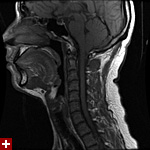

once i got back home and checked out my scans in osirix (the mac os x application to view DICOM medical imaging slides), i was blown away. talk about invasive: you haven't seen intimate until you've looked at photos of the inside of your body. the coolest part is since the scans were done in cross-sections, i can animate the scans so it looks like the beam is passing through my neck and head (all 800+ images). i've always known that inside my body was all sorts of muscles and veins and organs, but i guess i was hoping for something less messy, maybe circuit boards and memory chips instead. i know MRI's were first used in the late 60's, but this is my first time experiencing the technology in-person and it's pretty amazing. talk about futuristic! to be able to see with so much detail the insides of my body without having to cut me open! if scientists can do this, what else can they do? my only regret is they only imaged me from my shoulder up. i'd love to have a full-body scan. maybe i can fake some sort of internal injury and get my doctor to okay the procedure. i recommend anyone who's never had an MRI done to do so when they have the chance.

speaking of doctors, the main reason why i was at MGH this morning was for a follow-up appointment with my doctor. he basically told me that my MRI scans were fine as well as my blood work (he wrote me a letter a few weeks ago, so i already knew the news). since the pain in my neck had already disappeared,

i wasn't disappointment that we never figured out what was the cause. however, i did want to talk to him about the muffled hearing i've been experiencing in my left ear since as far back as october. he checked my ear and it seemed normal: no inflammation, no perforated eardrum. a look down my throat revealed nothing as well. lacking anymore clues he decided to throw a bunch of drugs at me to see if it'd clear up my sinuses, which seemed to be the root of the problem. besides taking some claritin-D (pseudoephedrine sulfate & loratadine), he also told me to take some sudafed as well (pseudoephedrine hydrochloride), a combination of antihistamine and decongestant. that's followed my some afrin nasal spray (oxymetazoline hydrochloride) plus the prescription strength nasal spray flonase (fluticasone propionate).